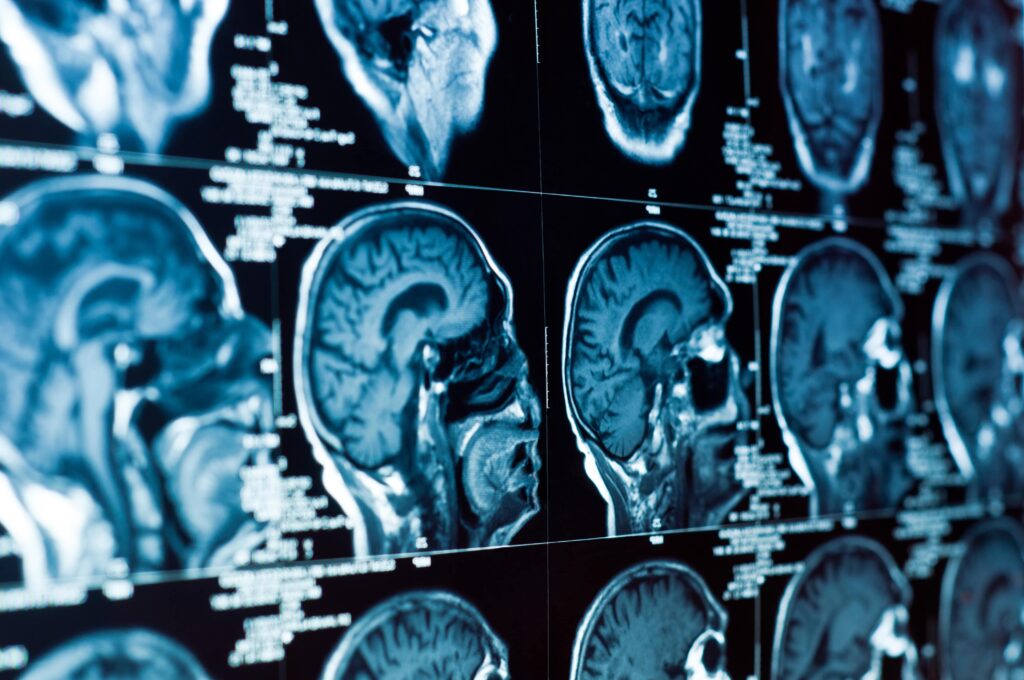

Traumatic Brain Injuries

Treatment options for brain injuries depend on injury severity. A patient with a mild injury may not need treatment other than rest and over-the-counter pain meds. Even with a mild brain injury, patients should have someone watch over them for signs of worsening or new symptoms.

Mild injuries may require follow-up doctor appointments so patients know when they can return to their usual daily routine. The first few days after a diagnosis, patients should take it easy on cognitive and physical activities, as they could worsen a brain injury. Patients must make sure they scale back on such activities, not refrain from them entirely. Those with moderate-to-severe brain injuries require emergency medical care to ensure they get enough oxygen and blood.

A personal injury lawyer could share stories about moderate-to-severe TBI patients who require medication. Because patients may experience seizures the first week after their injury, they may take anti-seizure medications. These prescriptions help limit further brain damage. To minimize fluid in tissues and boost urine production, medical care professionals could suggest diuretics.

Another benefit of the medication is it eases pressure inside the brain.

Sometimes, doctors recommend putting a brain injury patient into a temporary coma to minimize the amount of oxygen the brain needs to function. Increased brain pressure may squeeze blood vessels, which could constrict the nutrients and oxygen flowing to the brain.